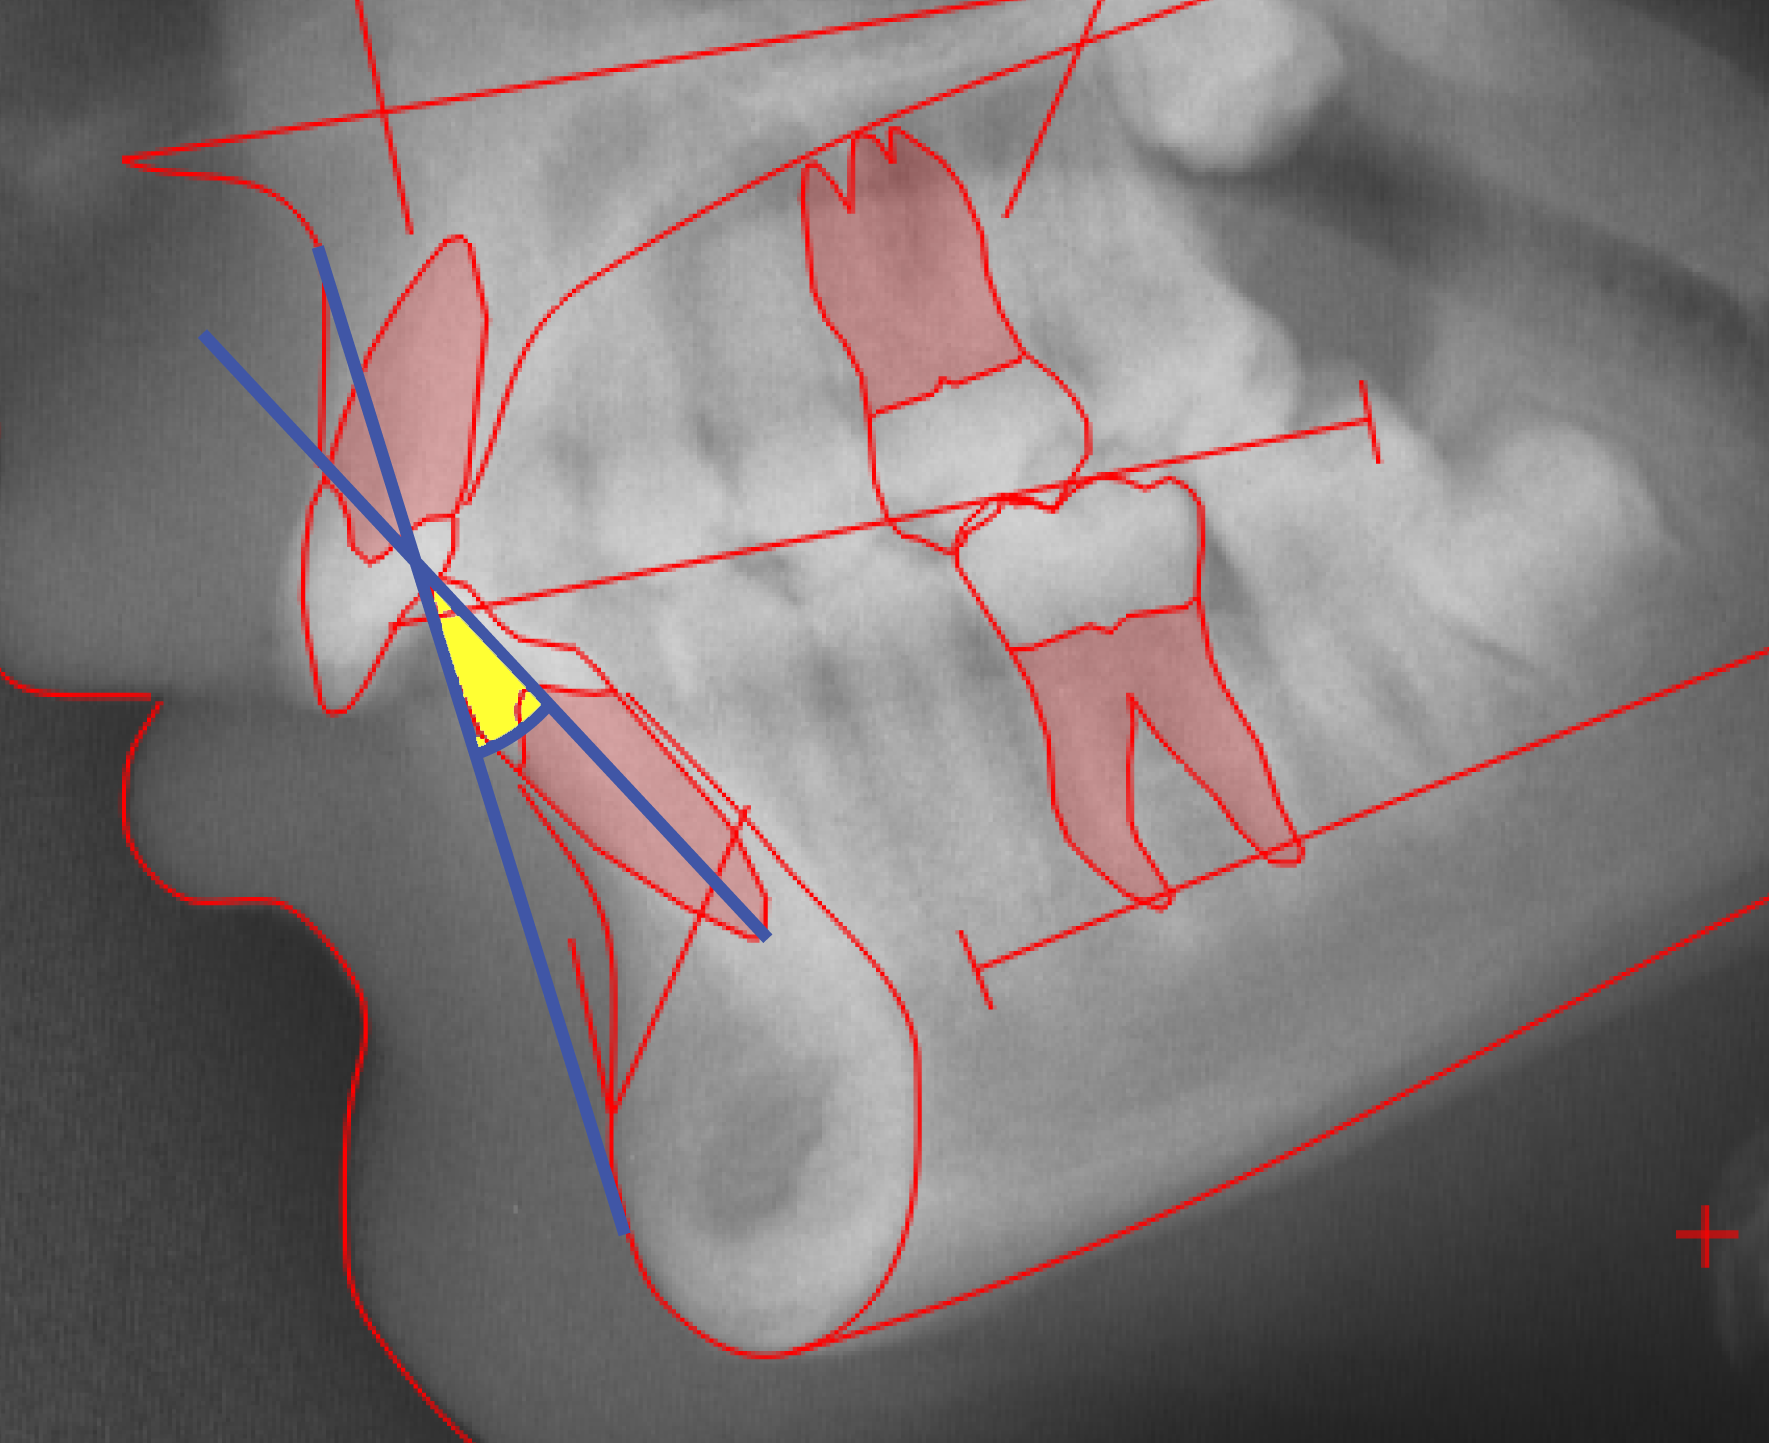

CEPHALOMETRIC MORPHOLOGICAL ANALYSIS

The illustations on this introduction page are discussed in detail in:

Cephalometric Morphological Analysis Parameters

Jens Bjoern-Joergensen, DDS, TIOPS ApS, Roskilde, Denmark

Ib Leth Nielsen, DDS, Division of Orthodontics, University of California, San Francisco

Example of variable values calculation sheet